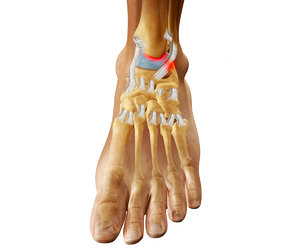

Артроз голеностопного сустава требует особого внимания потому, что его могут вызывать самые разнообразные причины. Причем это могут быть не только некогда полученные тяжелые травмы и избыточный вес. Благоприятствующими развитию этого заболевания факторами могут быть:

Травмы часто вызывают посттравматический артроз, который человек ощущает в виде отека левого или правого сустава. При отсутствии лечения к имеющейся болезни могут добавиться новые травмы, а это уже повышает риск развития воспаления — артрита.

Определить артроз можно по следующим признакам: